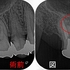

2026 EEdental NAM (3).jpg

仮歯で経過を見て、問題無さそうなので

硬質レジンでクラウンを作ります。

2026 EEdental NAM (4).jpg

レジンでクラウン作る理由は柔らかいから、ここにジルコニアなどの固い物をでクラウンを作ると

根の方に負担がかかり、すぐにダメになった経験があるので、わざとクラウンは弱目の材料を使い

クラウンをすり減らし、根の方への負担を軽減させます。